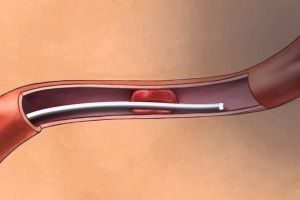

Темой очередного заседания неврологического общества г. Киева стала одна из наиболее насущных проблем неврологии и медицины в целом – вторичная профилактика инсульта.

В мире ежегодно регистрируется около 15 млн инсультов, в связи с инсультами умирают более 5,5 млн человек.

Качество медицинской помощи при инсульте может и должно быть улучшено – об этом говорят значительные различия показателей ежегодной заболеваемости и смертности в разных странах мира. Несмотря на то что в большинстве развитых стран действуют национальные..

В последние годы во всем мире прогрессивно возрастает количество мозговых инсультов (МИ), в первую очередь за счет ишемических нарушений мозгового кровообращения. В ближайшие десятилетия эксперты ВОЗ предполагают дальнейший рост количества ишемических...

Медико-соціальне значення проблеми судинних захворювань нервової системи визначається високою питомою вагою їх у структурі захворюваності та смертності населення, високими показниками первинної інвалідності. З-поміж усіх судинних захворювань головного...